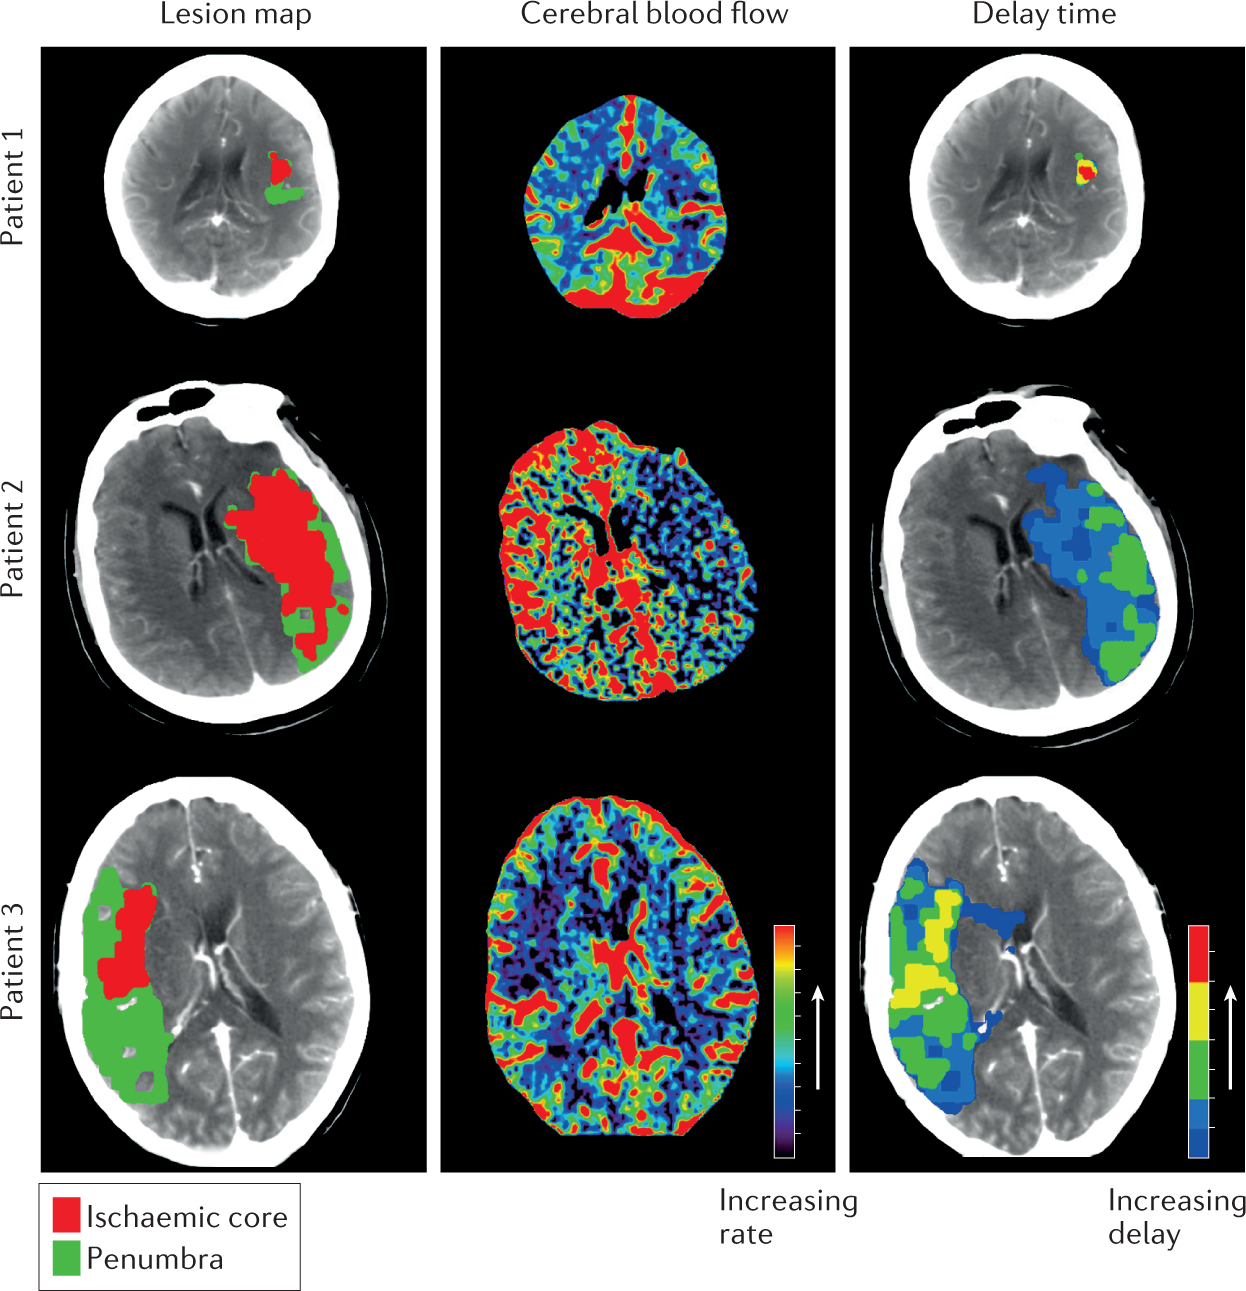

The medical world is now changing fast. AI is reading scans, new drugs are rewriting survival curves, and everyday decisions at the bedside are quietly being transformed.